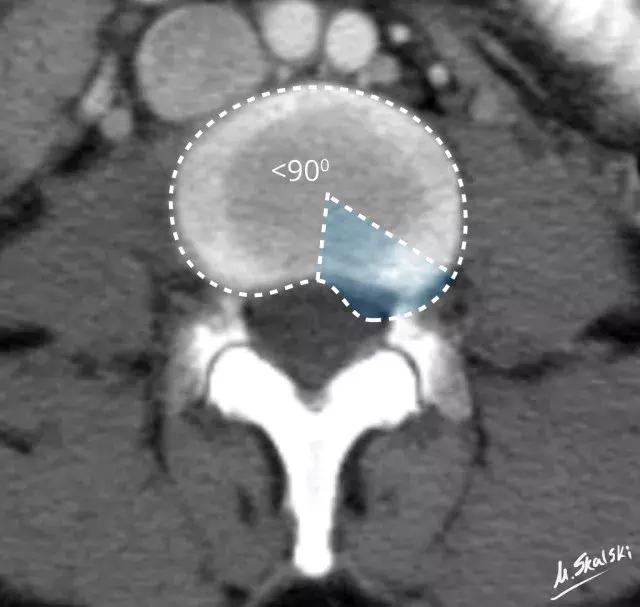

2. 椎间盘突出(Disc protrusion)

为髓核突入纤维环内但后纵韧带未破裂,表现为椎间盘局限性向椎管内突出。

图 4 椎间盘突出的影像学定义为突出部分小于椎间盘边缘的25%,并且基底部>突出部分的直径;突出椎间